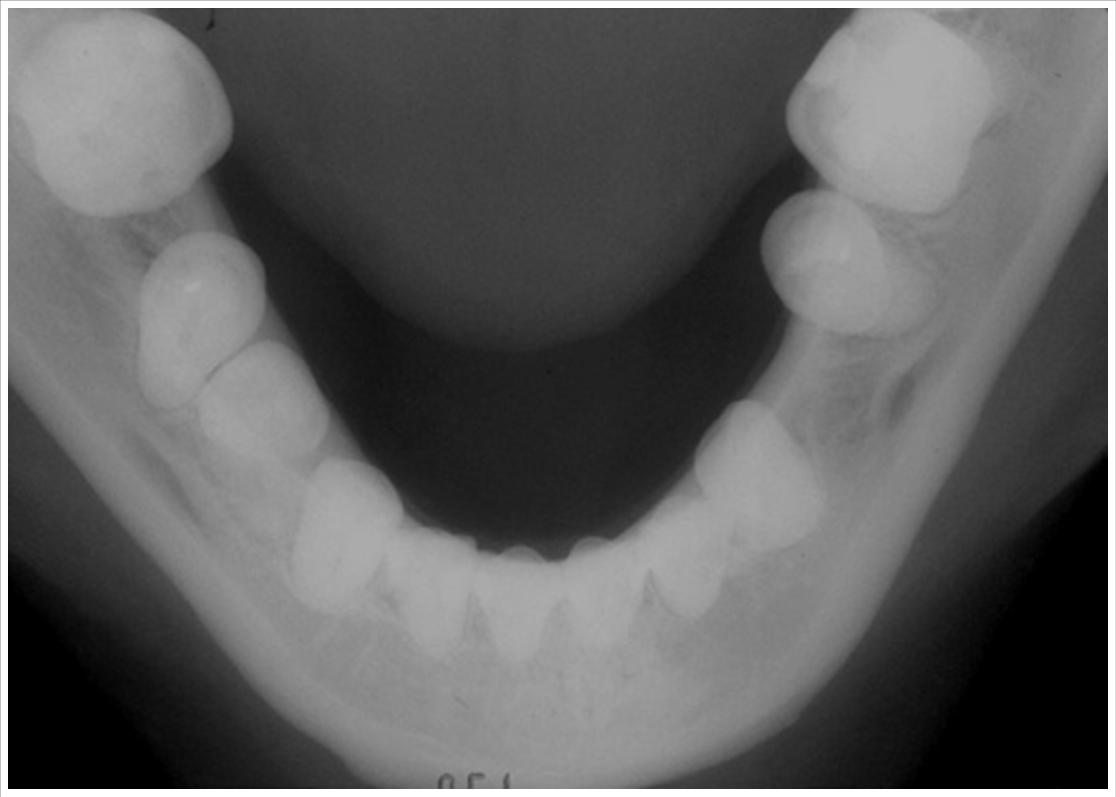

Debido a que trabajamos con la más avanzada tecnologia todas las radiografias digitales pueden ser entregadas/enviadas: Impresas en peliculas radiográficas con formato médico de alto contraste, CD y/o correo electrónico.